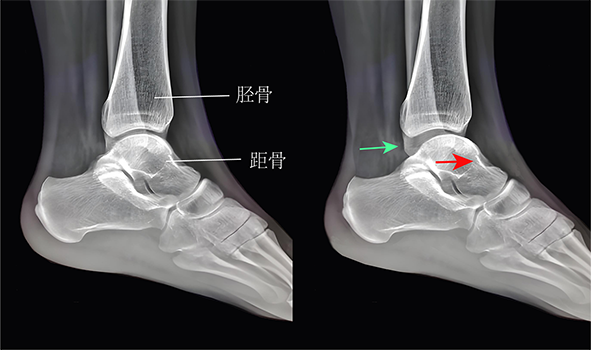

图1:踝关节外侧韧带示意图

图6:前抽屉试验

图7:距腓前韧带断裂或松弛时,抽屉试验可见距骨前移(右图,红色箭头),踝关节间隙增宽(绿色箭头)